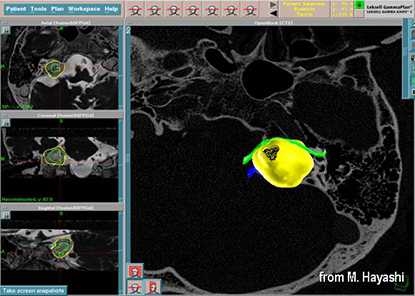

Следующим шагом после установки стереотаксической рамы, является получение серии изображений, на магнитно-резонансном (МРТ) томографе, иногда (дополнительно) компьютерном томографе (КТ), в некоторых случаях требуется проведение процедуры ангиографии. Данные исследования необходимы для определения точного размера, формы и положения опухоли. Во время получения серии диагностических изображений на стереотаксическую рамку помещается специальный координатный блок для определения контрольных точек, с целью создания плана лечения в специальной компьютерной программе. После КТ и МРТ процедур координатный блок снимается с рамы.

Создание лечебного плана пациента

Как только снимки будут сделаны, пациент может отдохнуть. В это время лечащий врач совместно с медицинским физиком разработают индивидуальный лечебный план для пациента. Создание плана проходит в специальной компьютерной программе, в которой можно оценить дозовое распределение в объеме головного мозга, а также дозовые нагрузки на окружающие ткани.

С помощью планирующей системы Gamma Planи автоматической позиционирующей системывозможно проводить очень точное облучение опухоли (точность 0,5 мм), избегаяповреждения черепных нервов и других важных отделов мозга.